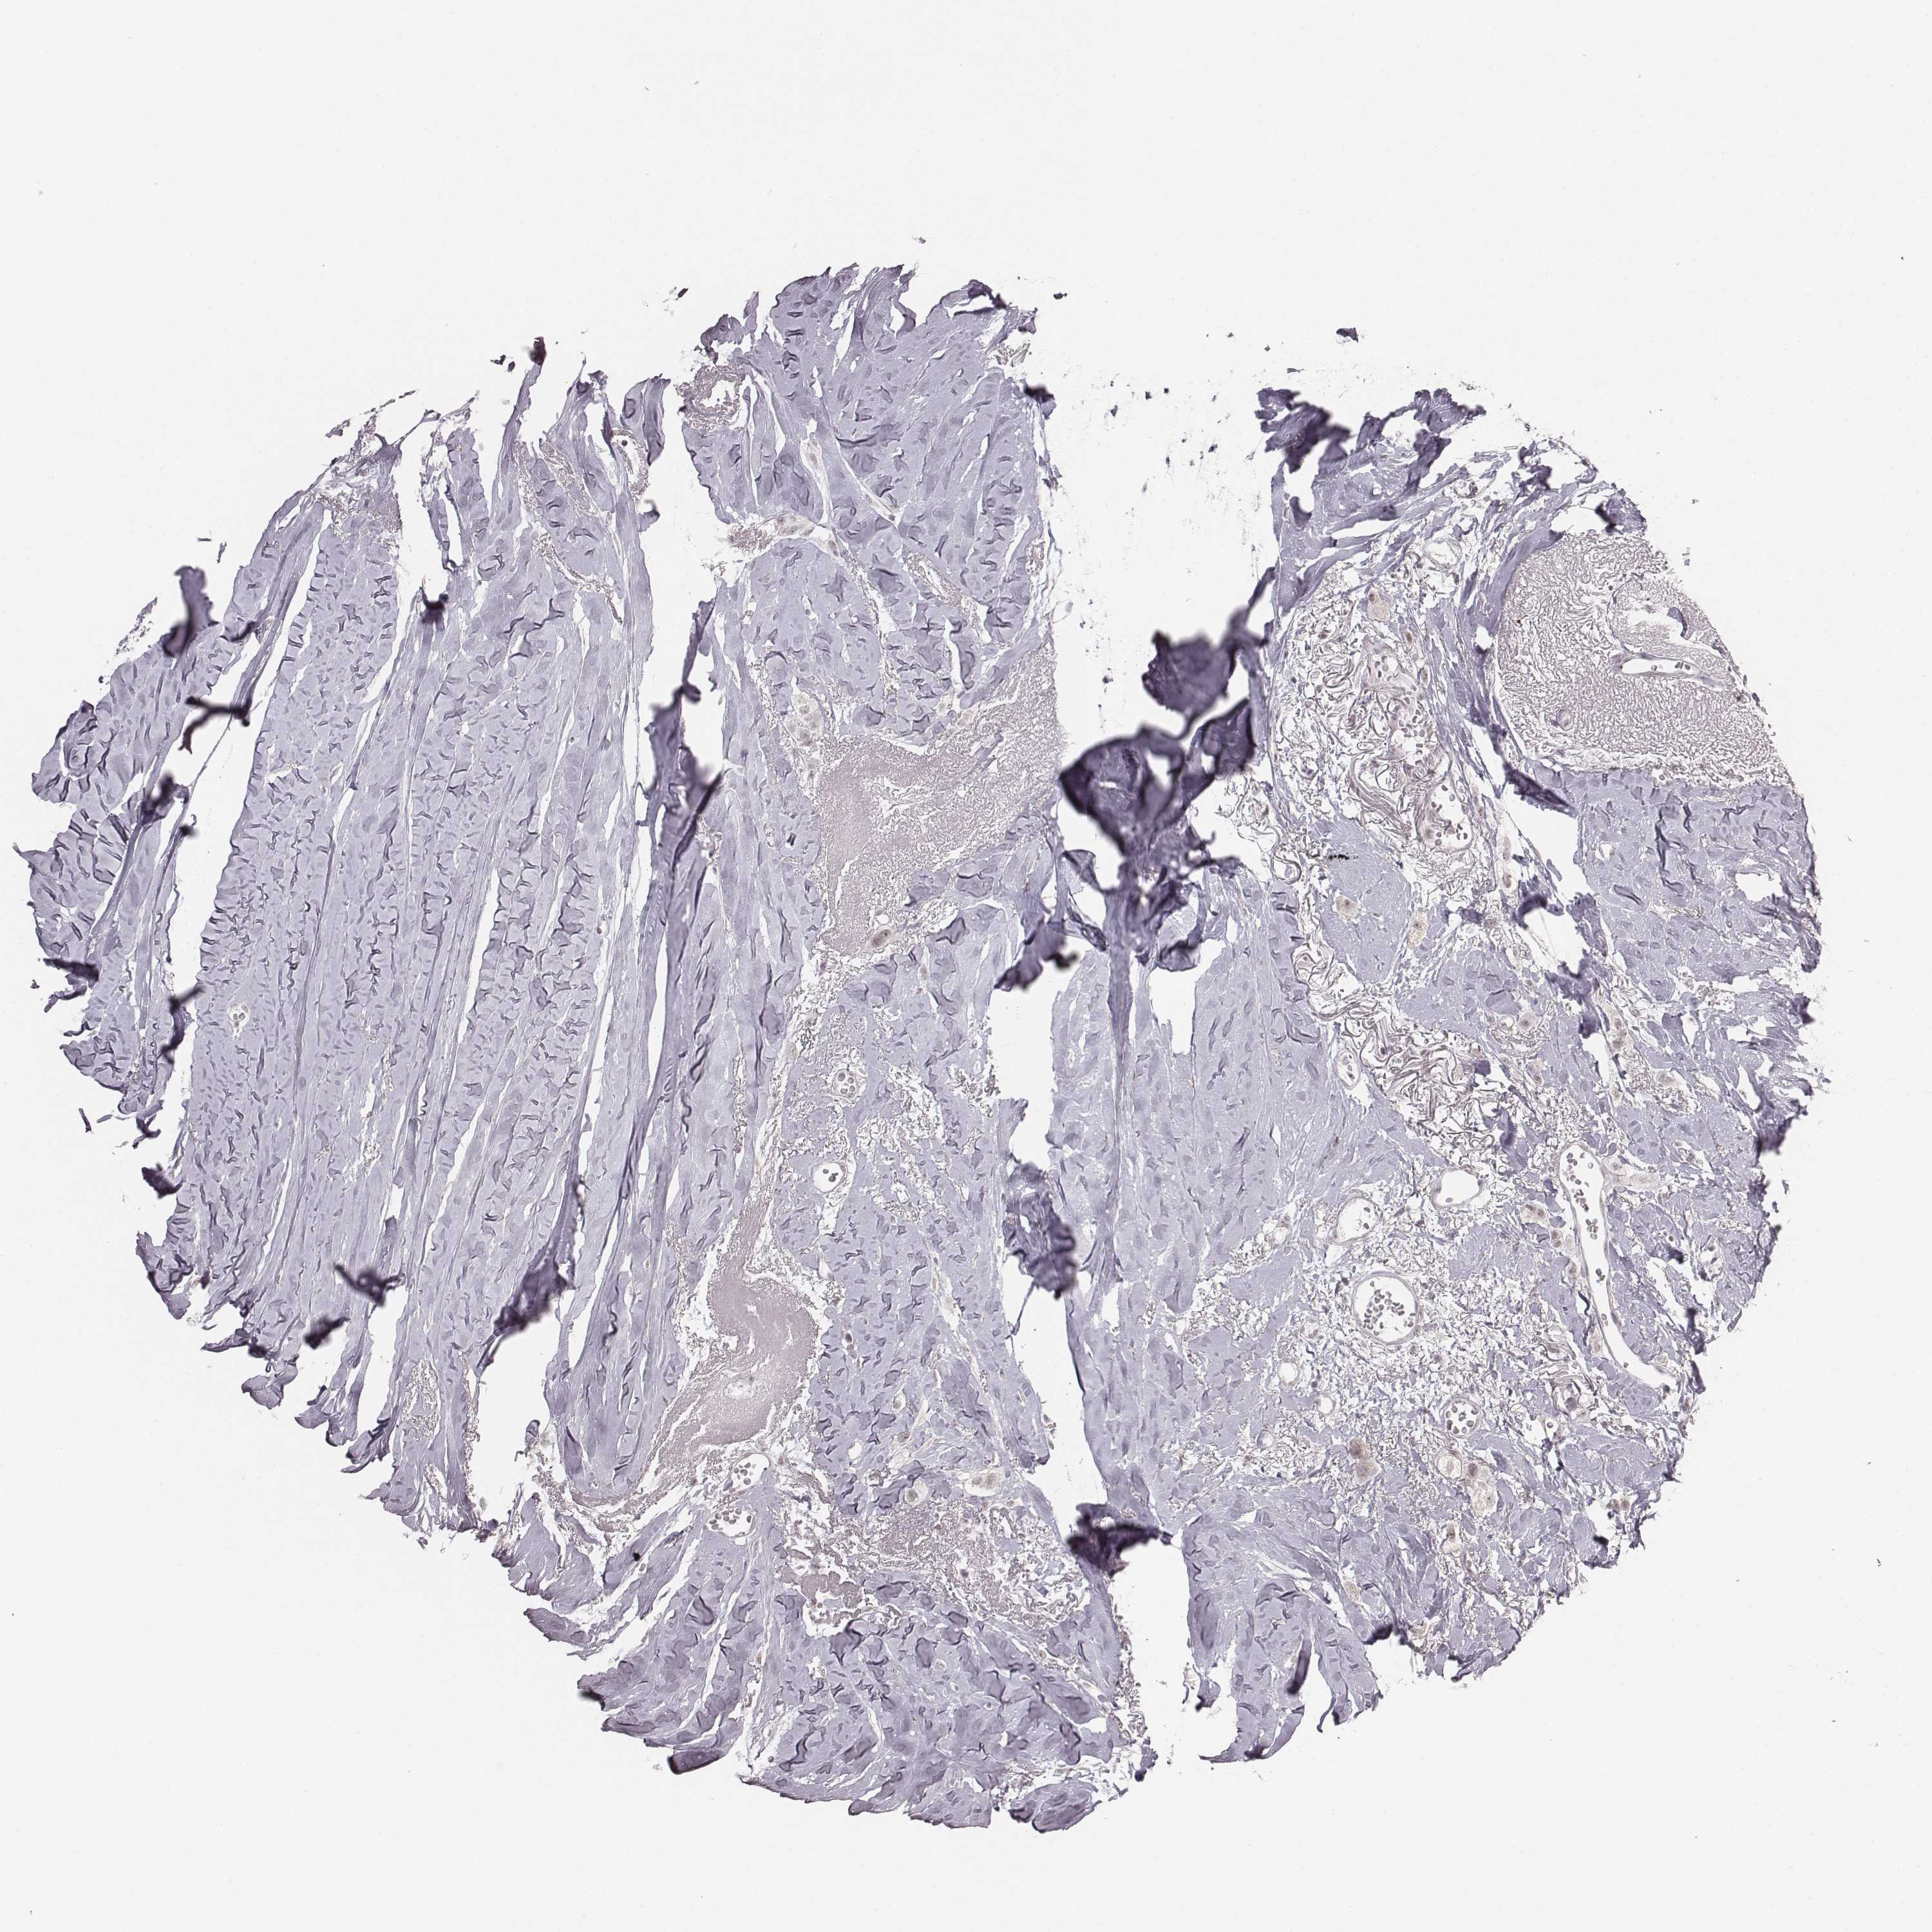

CANCER BREAST CANCER Show tissue menu

BRCA TCGA BRCA VALIDATION PROTEIN EXPRESSION

ANTIBODIES

AND

VALIDATION